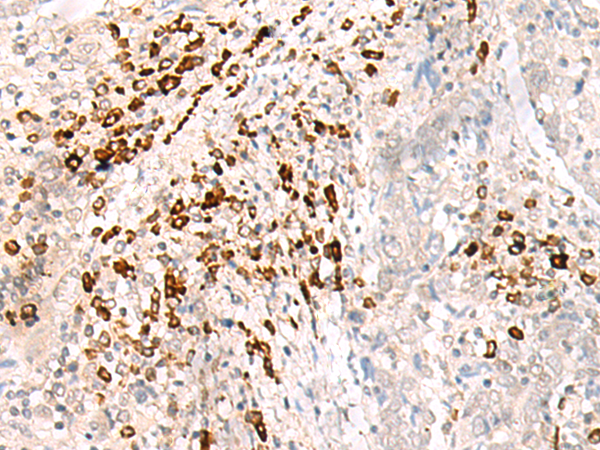

IHC positive control: |

Human cervical cancer |

IHC Recommend dilution: |

30-150 |